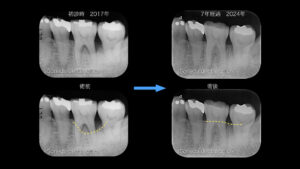

症例1 当院の歯周基本治療と咬合調整により歯を保存できた症例

術前は、黄色い線で示すように隣在歯にまたがる骨欠損(2壁性骨欠損)が認められました。

このような骨欠損形態では、再生療法の予知性は必ずしも高くないと考えられます。

また、本症例では咬合による影響が関与している可能性があったため、

骨形態だけでなく「力のコントロール」が重要と判断しました。

そのため、外科的介入は行わず、歯周基本治療と咬合調整を優先しました。

その結果、炎症の改善とともに骨レベルの回復が認められました。

✅7年経過しても安定した状態を維持しています。

また、このような骨欠損形態では再生療法の予知性が低いと考えられるため、

✅適切な診断により治療法を選択することの重要性が示唆されます。